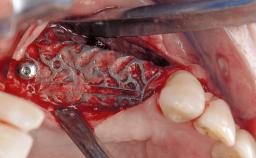

Peri-Implant Mucositis Associated with Misfit of a Cemented Restoration

A 37-year-old male patient was referred to the Department of Periodontology at the University of Bern, Switzerland, by a private dentist. Tooth 21 had been lost due to trauma and had been replaced with an implant and a cemented single crown. The tapered-effect tissue-level implant had a diameter of 4.1 mm, a length of 12 mm, and a sandblasted and acid-etched (SLA) surface (Straumann Dental lmplant System; Institut Straumann AG, Basel, Switzerland). The metal-ceramic crown had been cemented permanently, leaving a submucosal gap between the implant shoulder and the crown margin. Absence of marginal bone loss apical to the polished transmucosal neck of the implant could be observed .